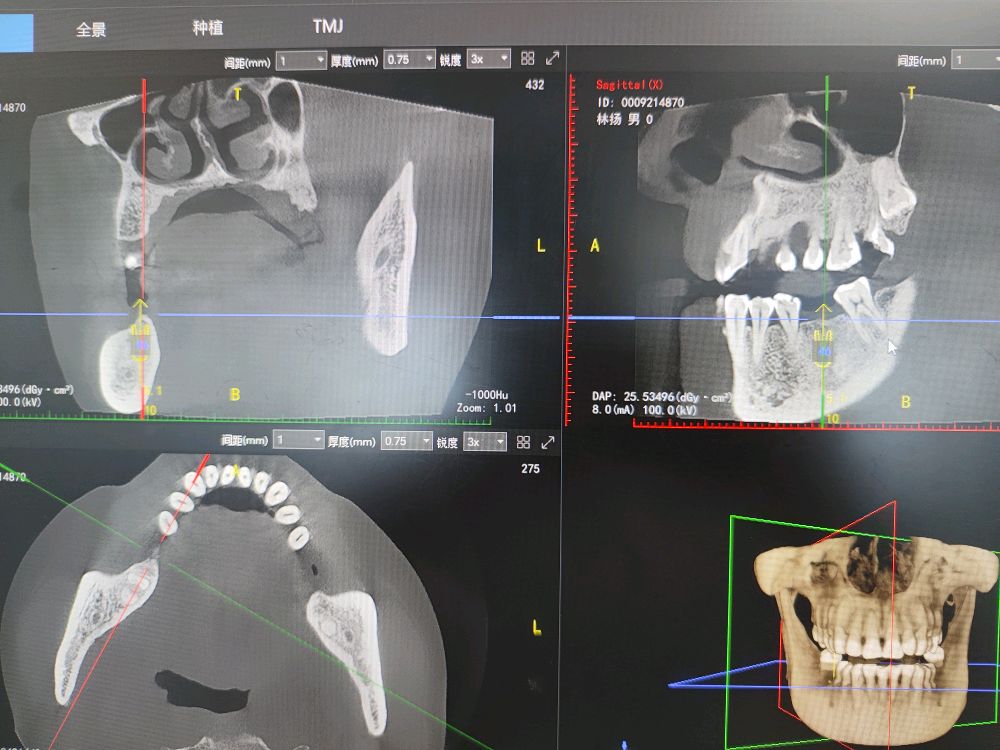

- 影像学检查:拍摄口腔全景片或CBCT(三维影像),评估骨量、神经位置。